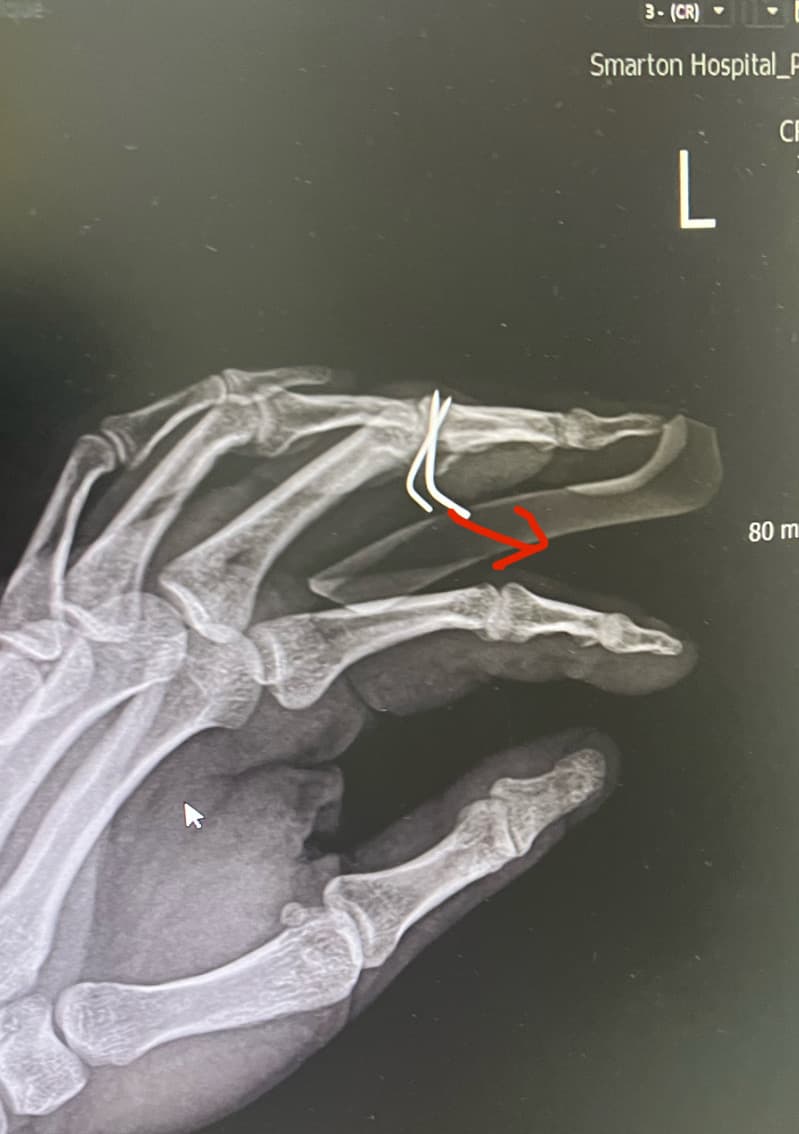

손가락 골절 수술 후 핀제거 했습니다.

1. 핀 제거를 하는데 원래 이렇게 아프게 뽑나요? 집도하신 원장님이 엑스레이 사진 빨간방향으로 잡아 땡기시더라구요.

그래서 제가 “그쪽방향이 아니다” 하니까 반대방향으로 빼던데 이사람이 집도한거 맞나요? 엑스레이도 봣으면서 왜 저 빨간방향으로 땡기는지.. 엄청아팟고 상처가 커졌습니다.

보통 핀을 뽑을 땐 약간의 통증이 동반되는것은 맞지만 핀을 박았을 때의 각도와 핀이 박힌 방향 그대로 빼는것이 맞지만 "ㄴ" 모양으로 되어있기에 다소 뽑을 때 통증이 동반됐을 가능성이 높습니다.